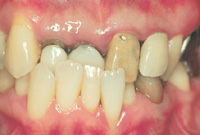

重度の歯周病患者さんの歯周組織改善の様子をみてみましょう!

当院来院時32歳。重度の歯周病です。特に歯列弓から飛び出している歯は、歯肉がかなり下がってしまっているのがわかります。